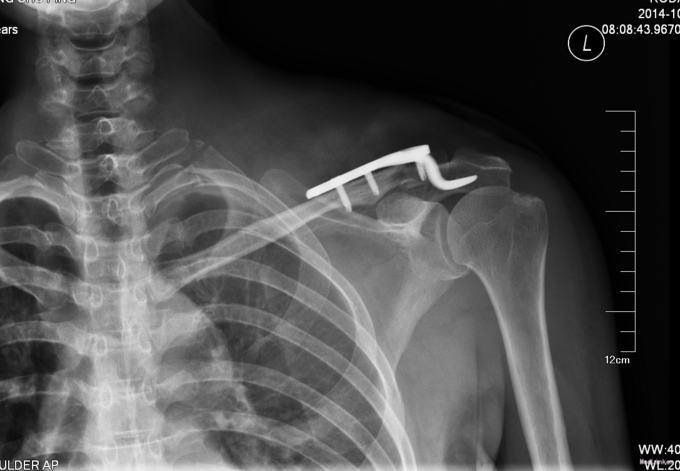

患者入院后完善相关检查,胸部CT报左气胸,请胸外科行闭式引流后,患者血氧约97%。择期行手术治疗。无其他手术禁忌症后行左锁骨骨折切开复位内固定术,术后3天后闭式引流液减少到10ml予以拔除。术后14天后出院。